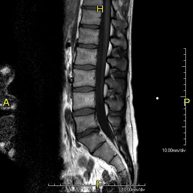

Prova diagnòstica no invasiva que consisteix en l'obtenció d'imatges d'alta definició anatòmica de la columna lumbar i sacre mitjançant l'ús d'un camp electromagnètic i ones de ràdio (amb un emissor i un receptor). No utilitza radiació ionitzant. Indicacions: traumatismes, ciàtica, hèrnies discals, tumors, infeccions - RM Mielografia

Prova diagnòstica no invasiva que consisteix en l'obtenció d'imatges d'alta definició anatòmica de la columna lumbar i sacre mitjançant l'ús d'un camp electromagnètic i ones de ràdio (amb un emissor i un receptor). No utilitza radiació ionitzant. Indicacions: traumatismes, ciàtica, hèrnies discals, tumors i infeccions. - RM de Sacre-còccix